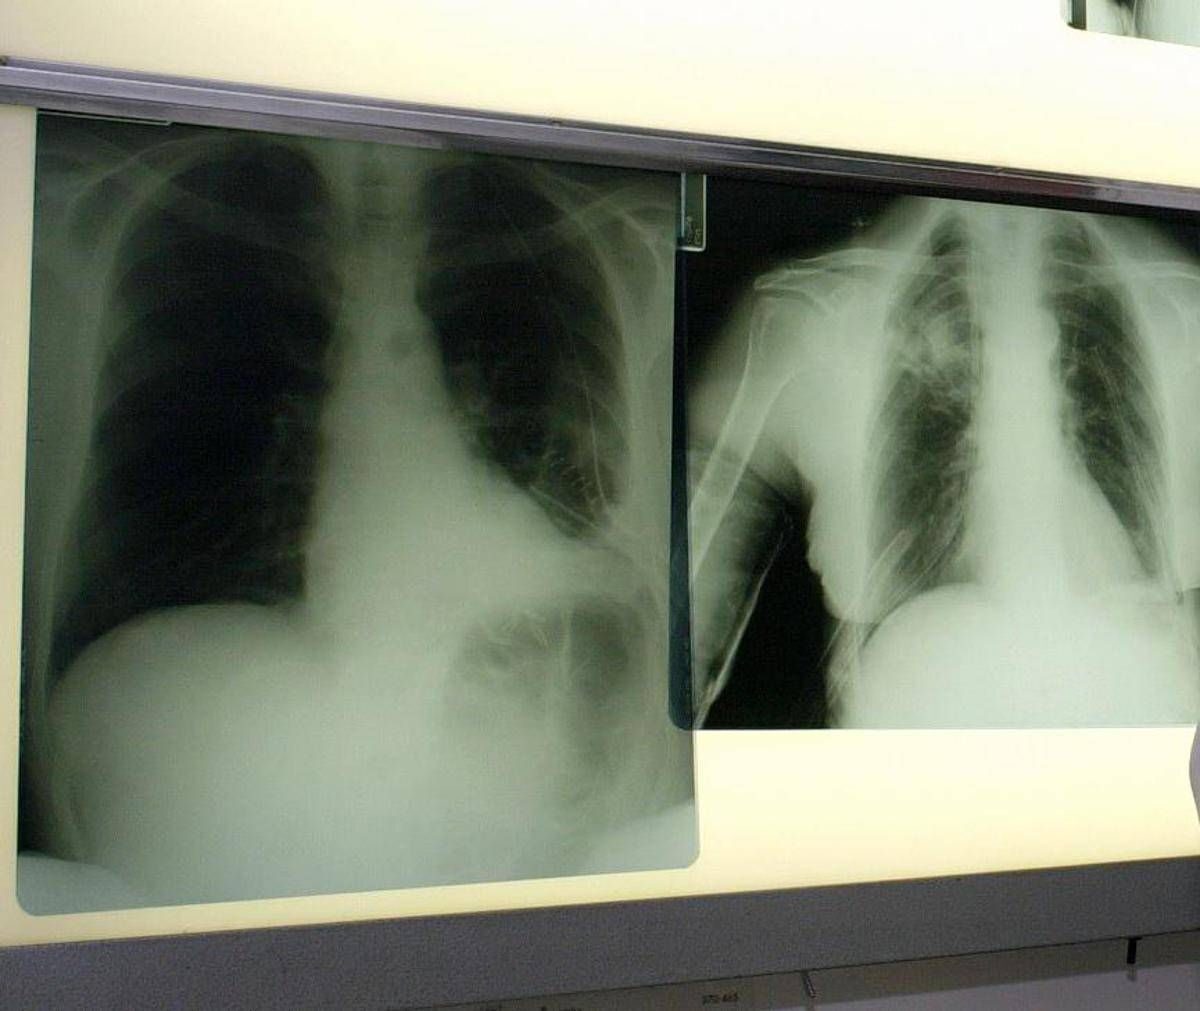

Il virus respiratorio sinciziale colpisce in modo diverso nelle differenti fasce d’età. L’Rsv “è un virus ubiquitario che colpisce praticamente tutti i bambini entro i 2 anni di vita, con possibili reinfezioni nel corso della prima infanzia e financo in età adulta – illustra Paolo Manzoni, professore associato di Pediatria e neonatologia, università di Torino – Se nei soggetti oltre i 2 anni di età il virus causa spesso sintomi simil-influenzali, colpendo per lo più le vie aeree superiori, al contrario una percentuale importante di pazienti con età meno di 2 anni presenta coinvolgimento delle basse vie aeree che può sfociare, nello specifico, nel quadro clinico classico conosciuto come bronchiolite e nelle sue complicanze sia immediate, sia a lungo termine”. Oltre ai neonati prematuri e di età inferiore ai 6 mesi, le popolazioni a rischio di sviluppare una patologia respiratoria grave a seguito di Rsv sono le persone over 60 e quelle immunocompromesse o con patologie preesistenti come il diabete, le malattie cardiache e polmonari, nelle quali il virus può scendere alle vie respiratorie inferiori causando principalmente polmonite.